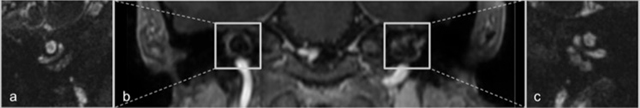

Figure 2

Coronal reconstructions of contrast-enhanced 3D FFE-imaging demonstrates symmetric areas of contrast enhancement in the pericochlear regions (b) Hyperintense signal anomalies are seen around the basal turn of the cochlea in the right (a) and left temporal bones (c) on 3D balanced steady-state gradient echo-imaging.

The MRI imaging of the temporal bone in OI patient with hearing impairment is characterized by symmetrical, bandlike alterations in the pericochlear areas. The affected regions demonstrate T2-hyperintense signal and homogeneous contrast enhancement. The hypothesis of enhancement after contrast administration is contrast pooling in the vascular channels in the improperly mineralized bone in addition to associated inflammation [3].